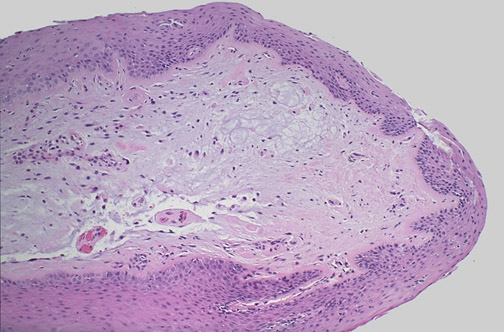

| Quiet! This is a laryngeal nodule (laryngeal polyp) that results most often from abuse of the voice (e.g., a "singer's nodule") or from smoking. Such polypoid lesions are typically found on the true cord and covered by squamous epithelium. They may impart a hoarse quality to the voice, but they do not result in malignancy, though larger ones (up to 1 cm) may ulcerate. |